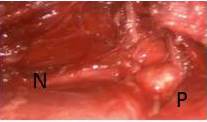

Se accede al tejido celular subcutáneo y posteriormente se visualiza los haces musculares del borde externo del músculo pectoral mayor. Usamos ópticas de 0 y 30 grados dependiendo del momento de la cirugía. La disección del tejido celular subcutáneo la hacemos conservando más o menos 1 cm de la piel y durante el avance hacia el cuello, el tejido mamario va quedando caudalmente no comprometiendo el mismo, hasta que visualizamos los haces musculares del borde externo del músculo esternocleidomastoideo, procediendo a separar anteriormente la rama esternal del mismo. Esto permite descubrir el borde lateral de la glándula tiroidea (Figura 6).

Ayuda una pequeña tracción del lóbulo contralateral tiroideo hacia el cirujano por parte del cirujano ayudante, para visualizar mejor la glándula tiroidea. Se usa cauterio monopolar y lo combinamos con bisturí armónico. La tiroidectomía se realiza de manera similar a la tiroidectomía abierta, evaluando localización del nervio laríngeo superior, recurrente y glándulas paratiroides (Figura 8).